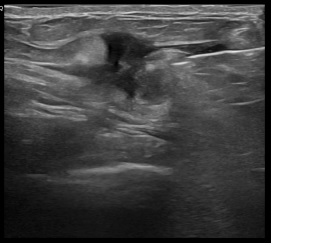

상기환자는 만져지는 멍울로  내원하신 30대초반

여성분으로 의심스러운 좌측혹 조직검사 시행해 침윤성암 으로 진단되었습니다